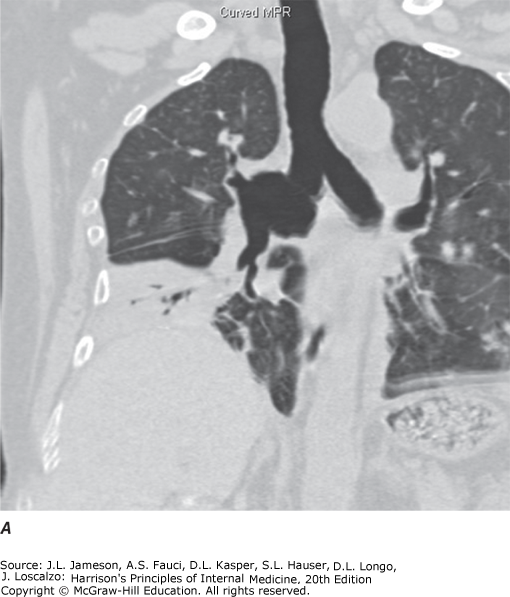

| 11 | Be familiar with diagnostic procedures in respiratory disease | Diagnostic modalities include imaging (chest X-ray, CT/helical CT, MRI, ultrasound, nuclear medicine/V-Q scan, PET scan, virtual bronchoscopy) and tissue-sampling techniques. CT is superior to plain film for mediastinal disease, emphysema characterization, and lung cancer staging. MRI excels at vascular assessment without contrast. |

| CT | Cross-sectional images distinguish superimposed densities. Far better tissue density characterization and accurate lesion sizing than plain film. With IV contrast: distinguishes vascular from nonvascular structures | Hilar/mediastinal disease, lung cancer staging, pulmonary embolism, pulmonary nodule characterization |

| Helical/MDCT | Standard method for thoracic CT. Faster scans, single breath-hold acquisition, less motion artifact, thinner collimation. Data reconstructed in coronal and sagittal planes | Standard thoracic CT method, continuous volumetric data acquisition |

| Virtual Bronchoscopy | 3D reconstruction from MDCT data. Visualizes airways down to 6th–7th generation. Digital storage allows reanalysis. Assesses airway relationship to mediastinal structures | Airway stenosis assessment (extent and length), pre-procedure planning for therapeutic bronchoscopy |